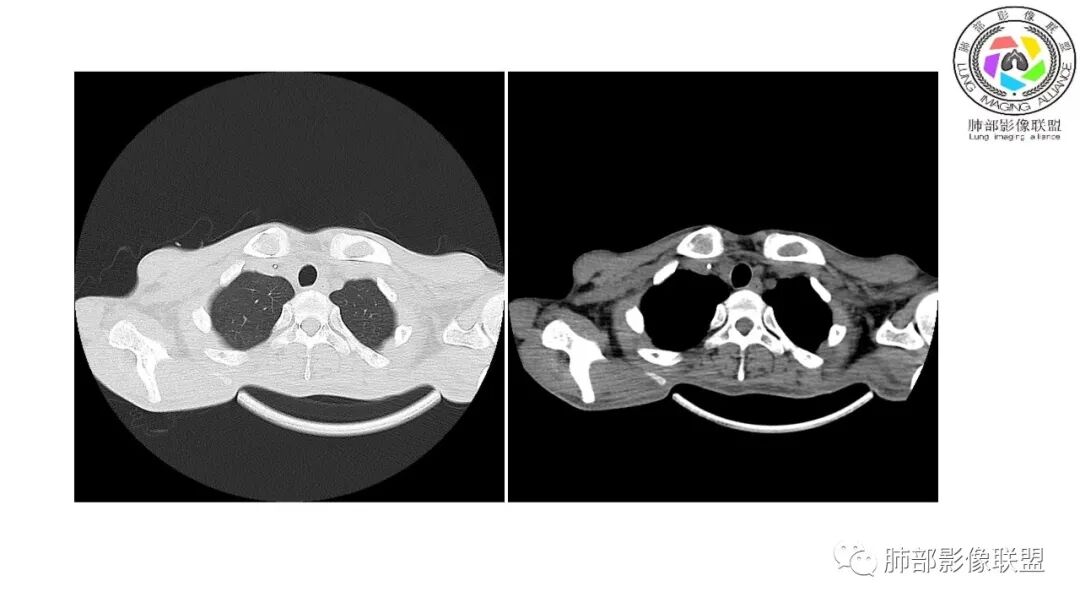

影像与临床:1.青年男性,HlV阳性,颜面部皮疹(未提供皮疹图像)、发热(高热),实验室CRP、PCT高,T-Spot阴性。2.右肺下叶空洞结节,壁厚不均,边界清楚,其内线状影,未见液平及钙化,未见卫星灶,纵隔淋巴结增大,双侧腋窝见增大淋巴结。心腔内低密度提示贫血可能。肝脾影增大,未见结节影及块影。腹膜后见多发增大淋巴结。

综合分析:本例肺部影像学改变并不具有特征性,空洞性病灶须与多种疾病鉴别,但年轻HIV阳性患者,高热,皮疹,肝脾增大,纵隔、腋窝、腹膜后见多发增大淋巴结等都强烈提示马尔尼菲篮状菌感染的可能性。